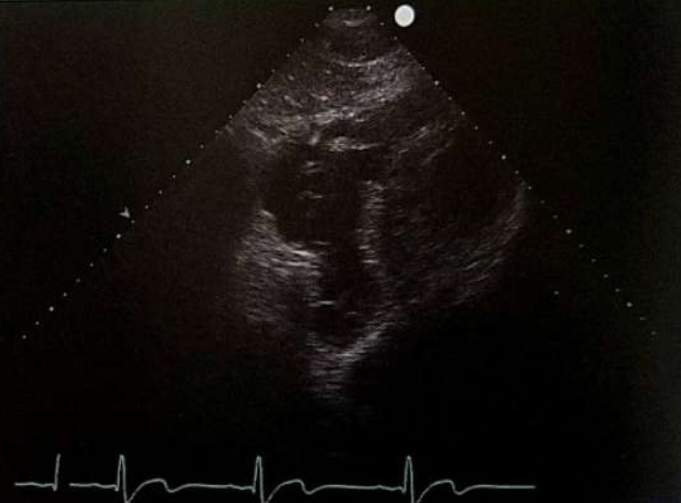

<p>What view would be obtained here?</p>

What view would be obtained here?

Subcostal 4ch View

<p>What view is this?</p>

What view is this?

Subcostal 4ch